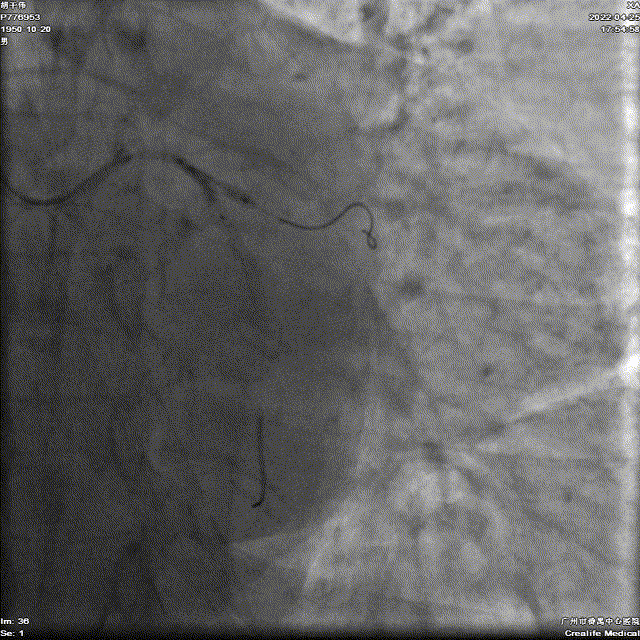

FFR